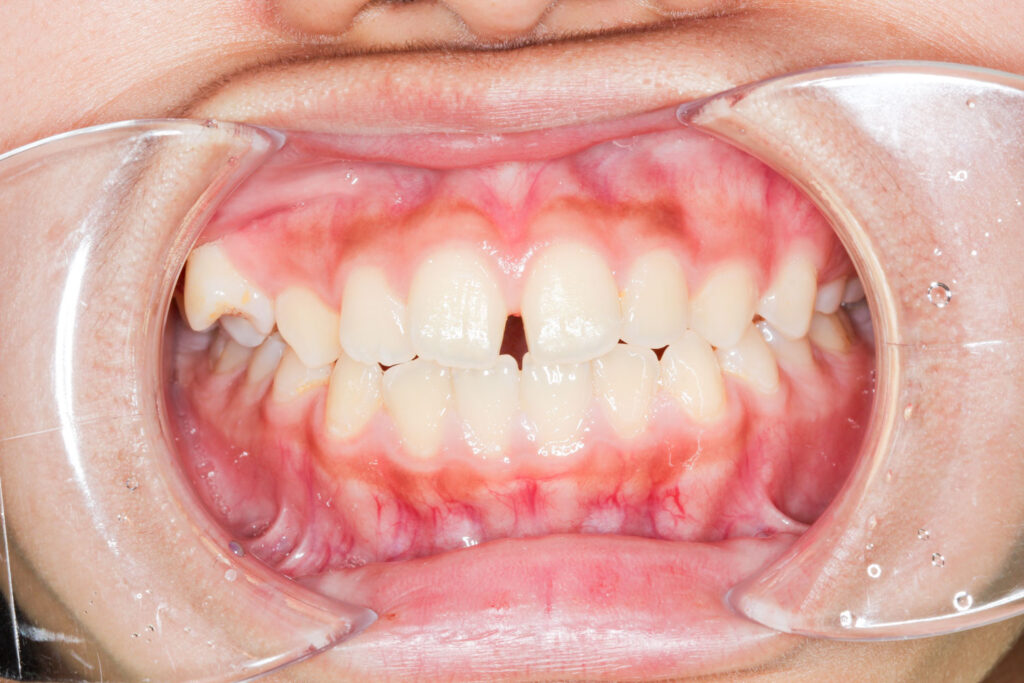

Before

After

年齢 10代

治療装置 表側の矯正装置(ホワイトコース)

治療内容 上下左右4本抜歯

治療期間 2年1か月

リスク 歯の移動に伴う痛み、歯肉退縮、歯根吸収、歯肉炎、虫歯

主訴 ガタガタが気になる

症状 叢生(ガタガタ)

治療回数 25回程度

総額費用 105万円程度